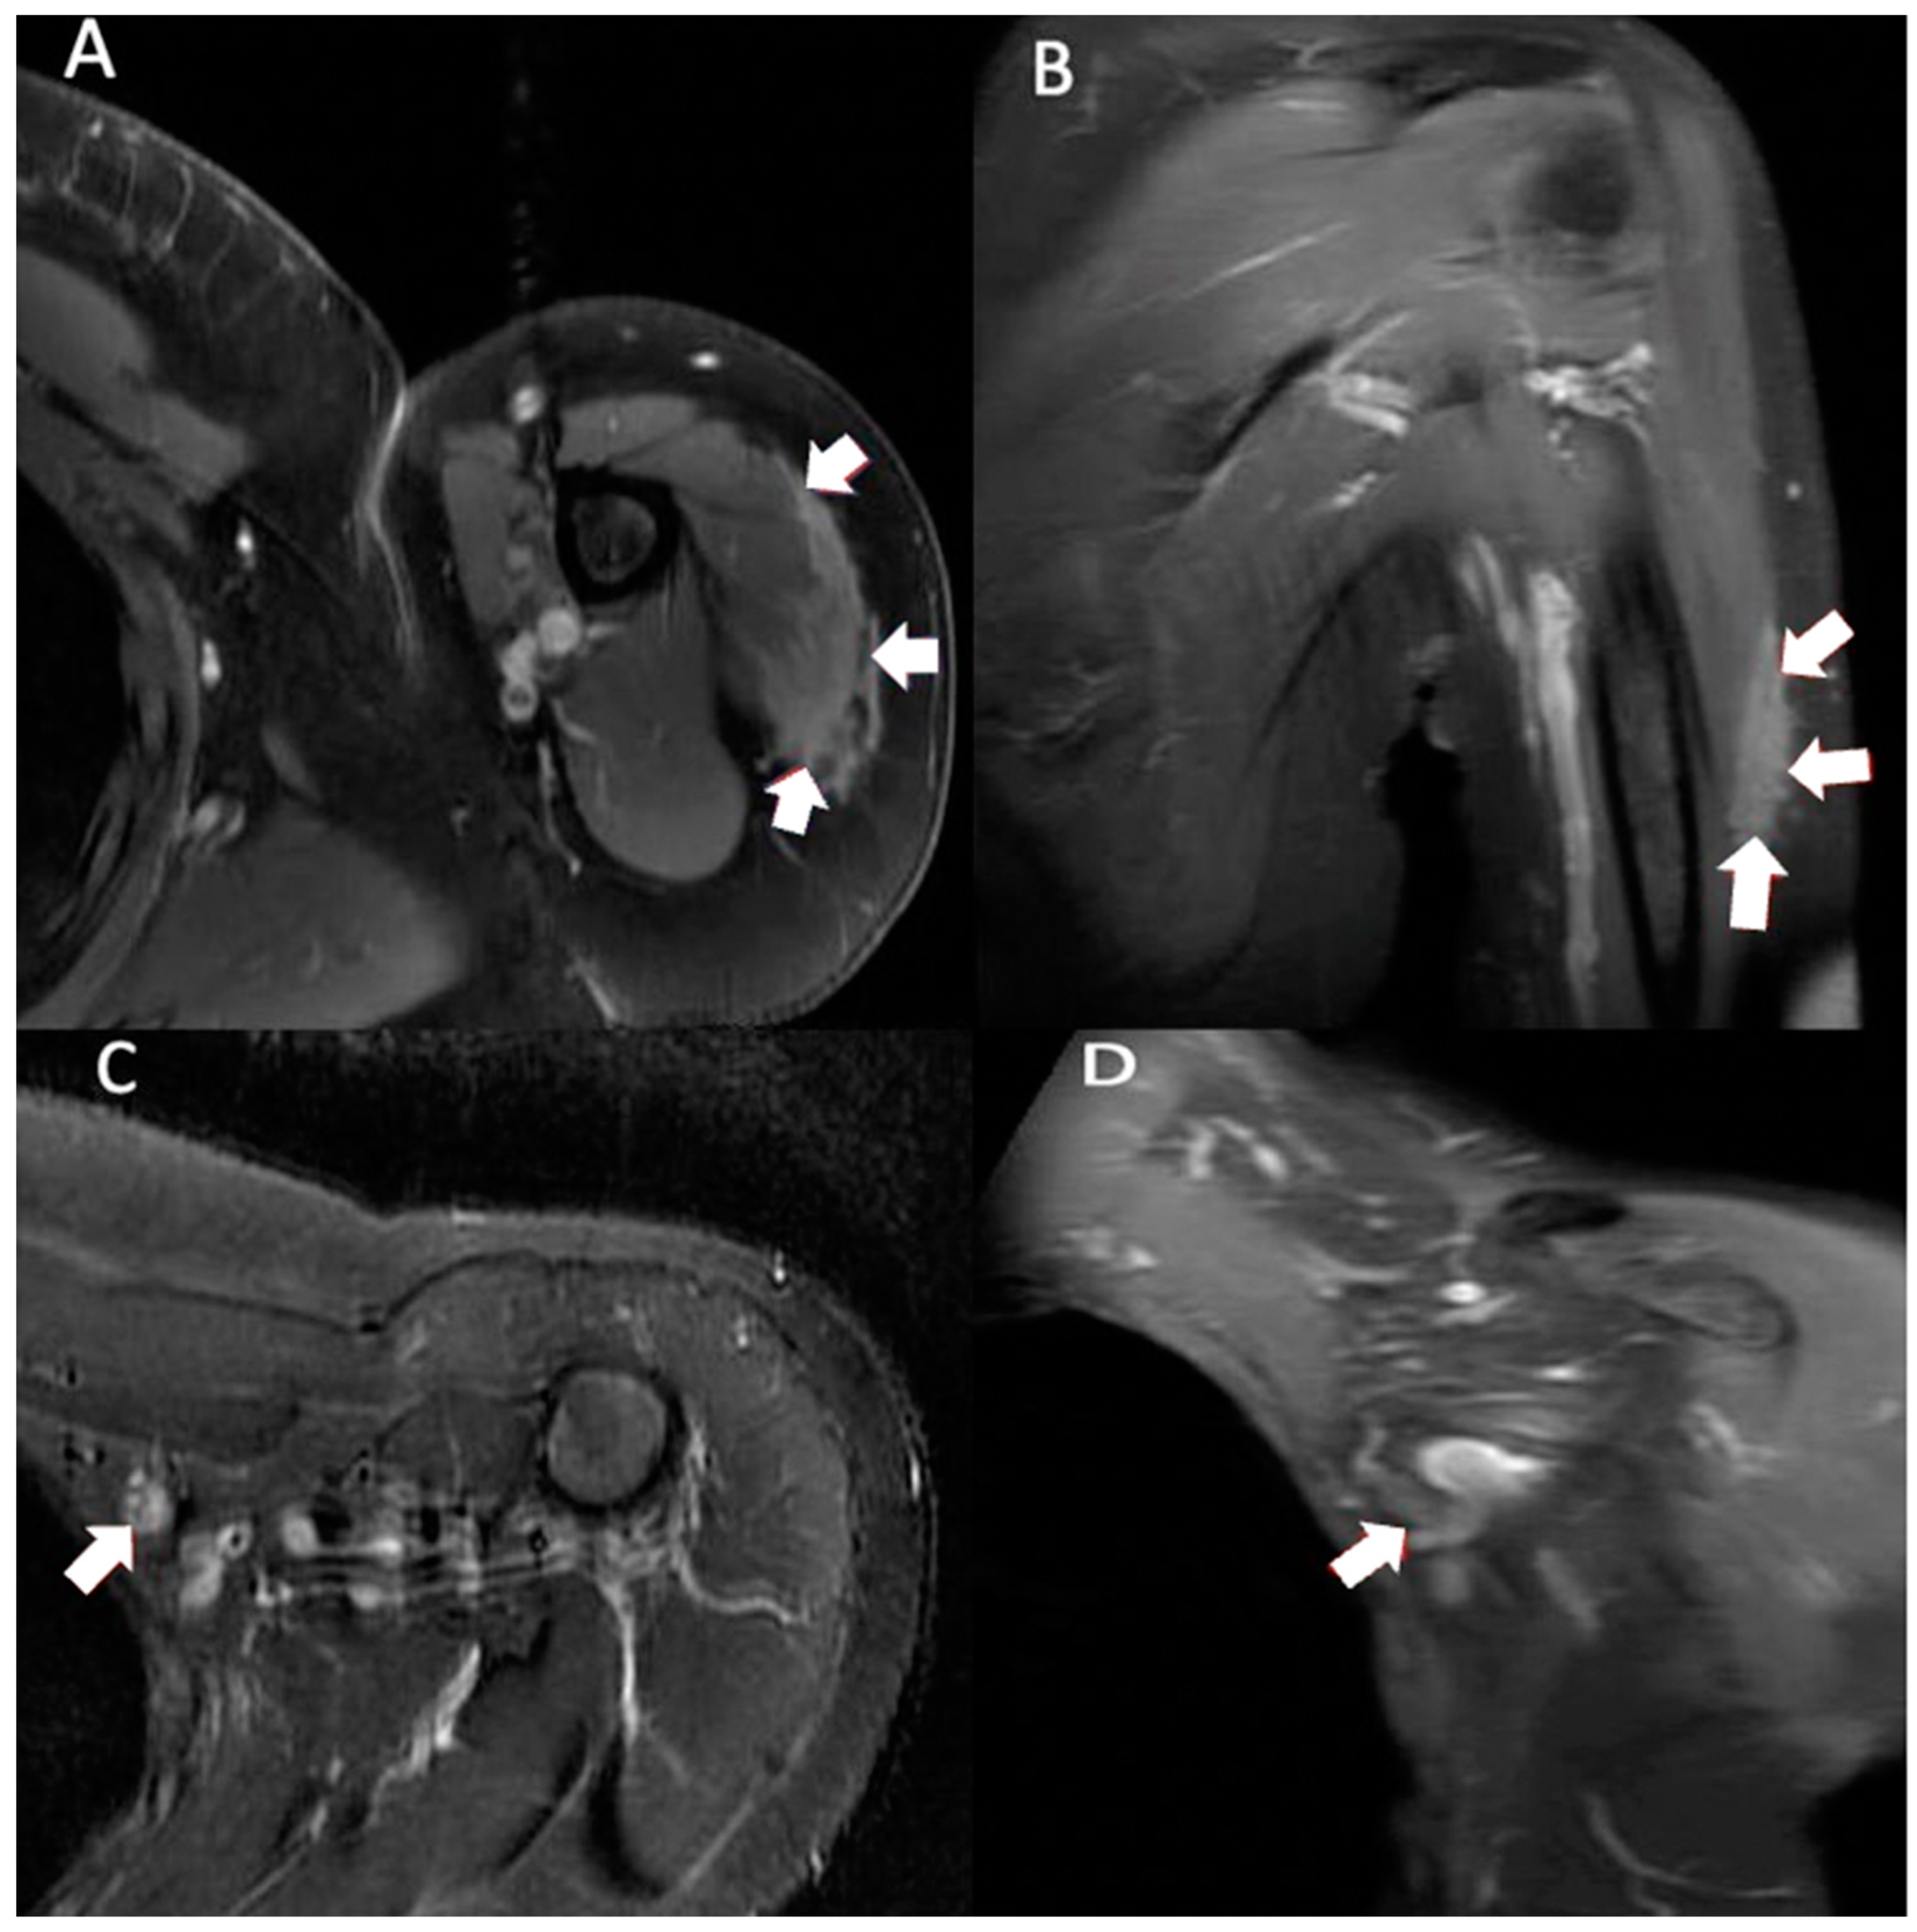

Figure 1. Multiplanar MRI of right shoulder taken 8 months after vaccine administration in right shoulder. Axial T2 (A) and coronal T2 (B) images show ill-defined fluid signal surrounding interspersed areas of fat. The involved area extended from surgical neck of the humerus to distal diaphysis, measuring approximately 14.9 × 8.2 × 1.8 cm (arrows).

Initially unconcerned of her symptoms, the patient took intermittent Tylenol for the pain and initiated a home exercise program. She had an appointment with her primary care physician (PCP) for an annual check-up 2 months after the symptoms had developed (4 months after completing the injections). Her PCP referred her to orthopedics due to concerns of bilateral shoulder pain and swelling of unknown etiology. She waited another 3 months before consulting orthopedics. By this time, her pain ceased but the bilateral swelling persisted. Her initial treating orthopedic surgeon ordered a right shoulder magnetic resonance imaging (MRI) to rule out malignancy on the more swollen side. The imaging showed abnormal regions within the subcutaneous tissue at the sites of the mass (Figure 1). Subcutaneous edematous tissue extended from the level of the humeral surgical neck to the distal diaphysis. Minor laboratory abnormalities of uncertain significance were noted in bloodwork that were obtained seven months after the second injection (Table 1). Based on the imaging findings in the context of her history of vaccination into the deltoids and improvement in pain over time, her idiopathic reactions were associated with the vaccination, and so, no biopsy was carried out, and observation was elected.